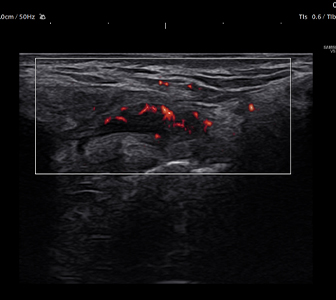

微小血流や低流速血流を可視化。